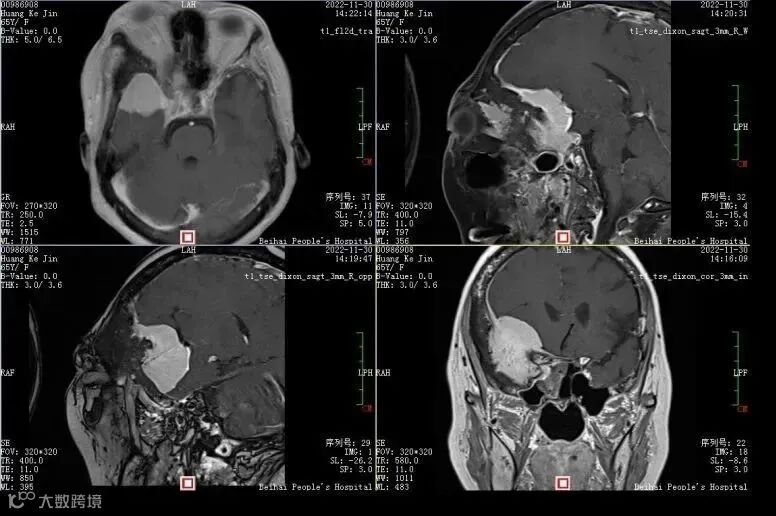

术前磁共振检查更清楚显示颅内及右侧眶内、蝶窦内广泛侵袭,局部颅骨增生明显。

由于病情复杂,医院组织神经外科、耳鼻喉科、眼科、放射科、肿瘤科、放疗科、病理科等多学科会诊,制定科学合理的治疗方案。与患者及家属充分沟通后,家属选择了手术治疗。

完善各项术前准备后,12月12日,邓峰、莫贻敏、邓喆等医务人员为患者进行手术,采用右侧翼点入路,术中用高速微型磨钻磨开颅底及右侧眼眶上壁和外侧壁,显微镜下蝶鞍旁、眶内、蝶窦病损切除手术及神经减压术,切除肿瘤大小约4*3cm,手术持续六个小时顺利完成。